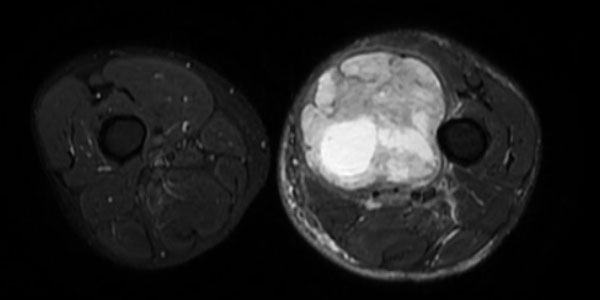

Liposarkom

Kötü huylu yumuşak doku tümörleri arasında ikinci sıklıktadır. Nedeni tam olarak bilinmemektedir. Çok farklı yaşlarda görülebilir fakat sıklıkla 40 yaş sonrası ortaya çıkar.